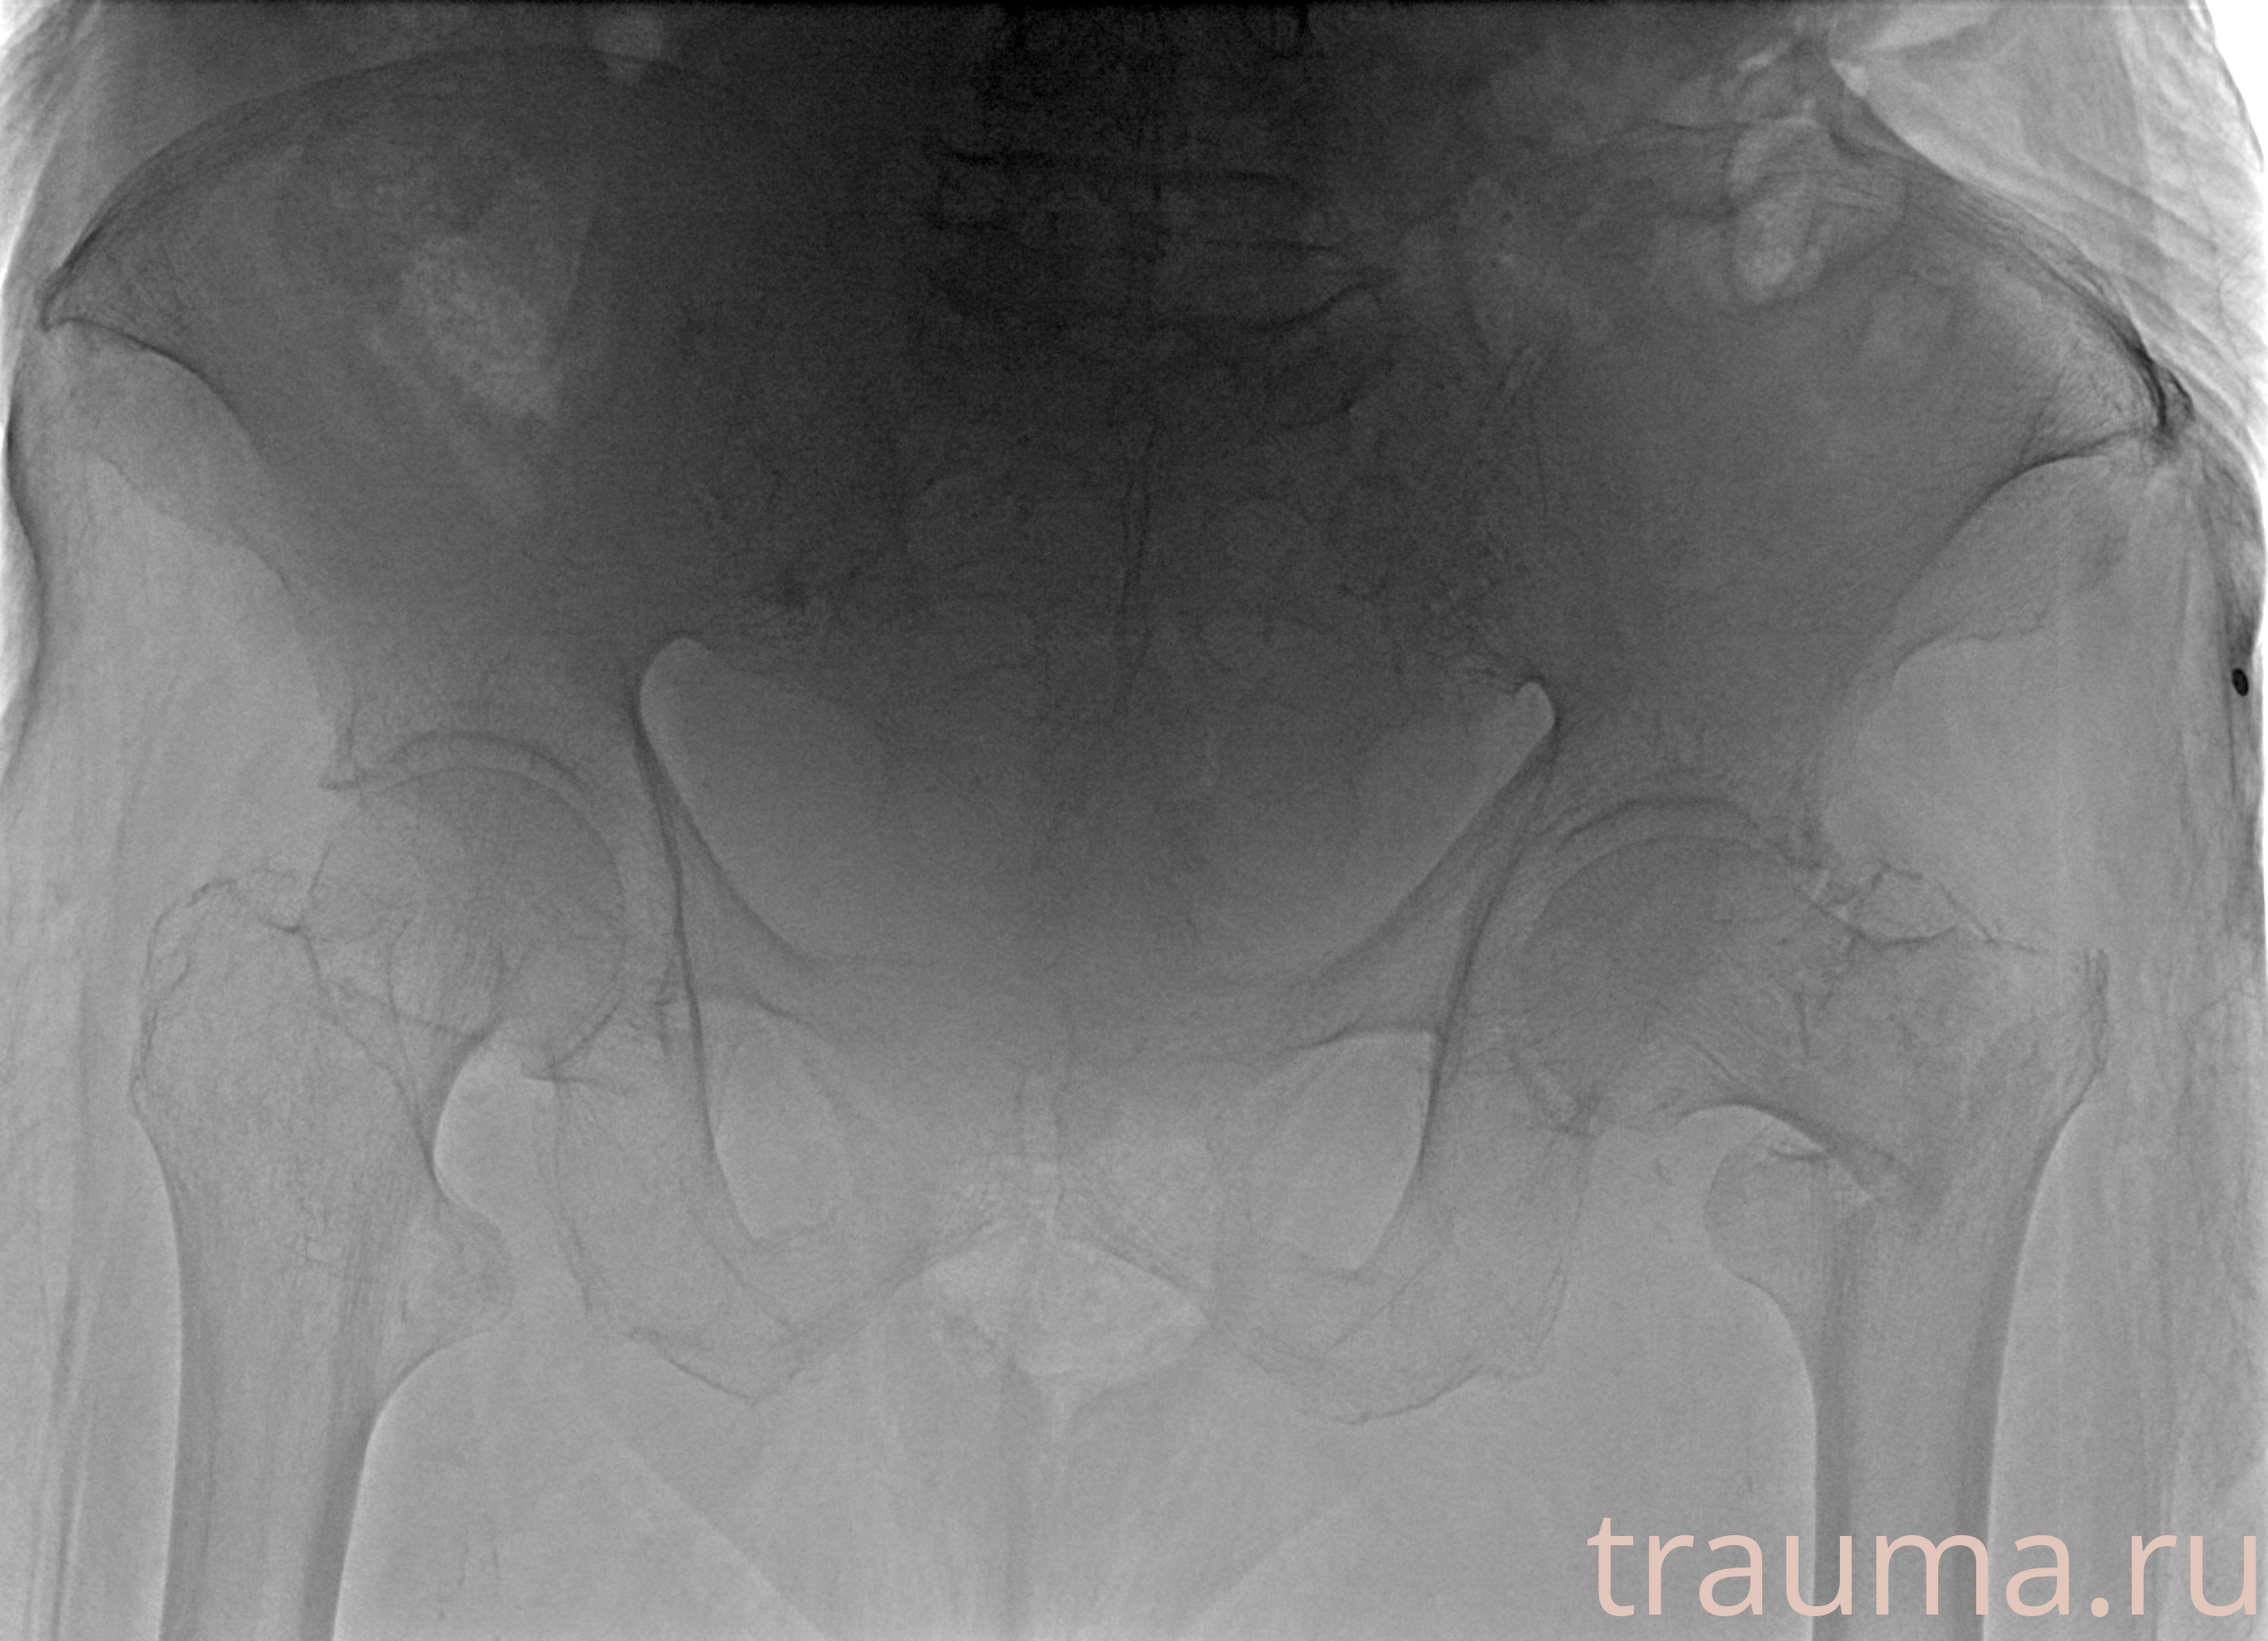

Рентгенограммы

Рентген на дому: по вашему адресу приезжает врач-рентгенолог, травматолог-ортопед с мобильным рентгеновским аппаратом, проводит диагностику травмы или заболевания, делает необходимые рентгенограммы, дает рекомендации по дальнейшему лечению. Получить качественные снимки в домашних условиях возможно благодаря уникальной методике, разработанной МосРентген Центром для института  Склифосовского

Яркость: 1   Контраст: 1   Инвертировать: 0 Увеличение: 1

Перетаскивайте мышь вверх/вниз для контраста, влево/право для яркости. Прокрутка колесом изменяет масштаб. Нажмите Сбросить для возврата к исходному изображению. При увеличении держите мышь в той области, которую хотите рассмотреть.